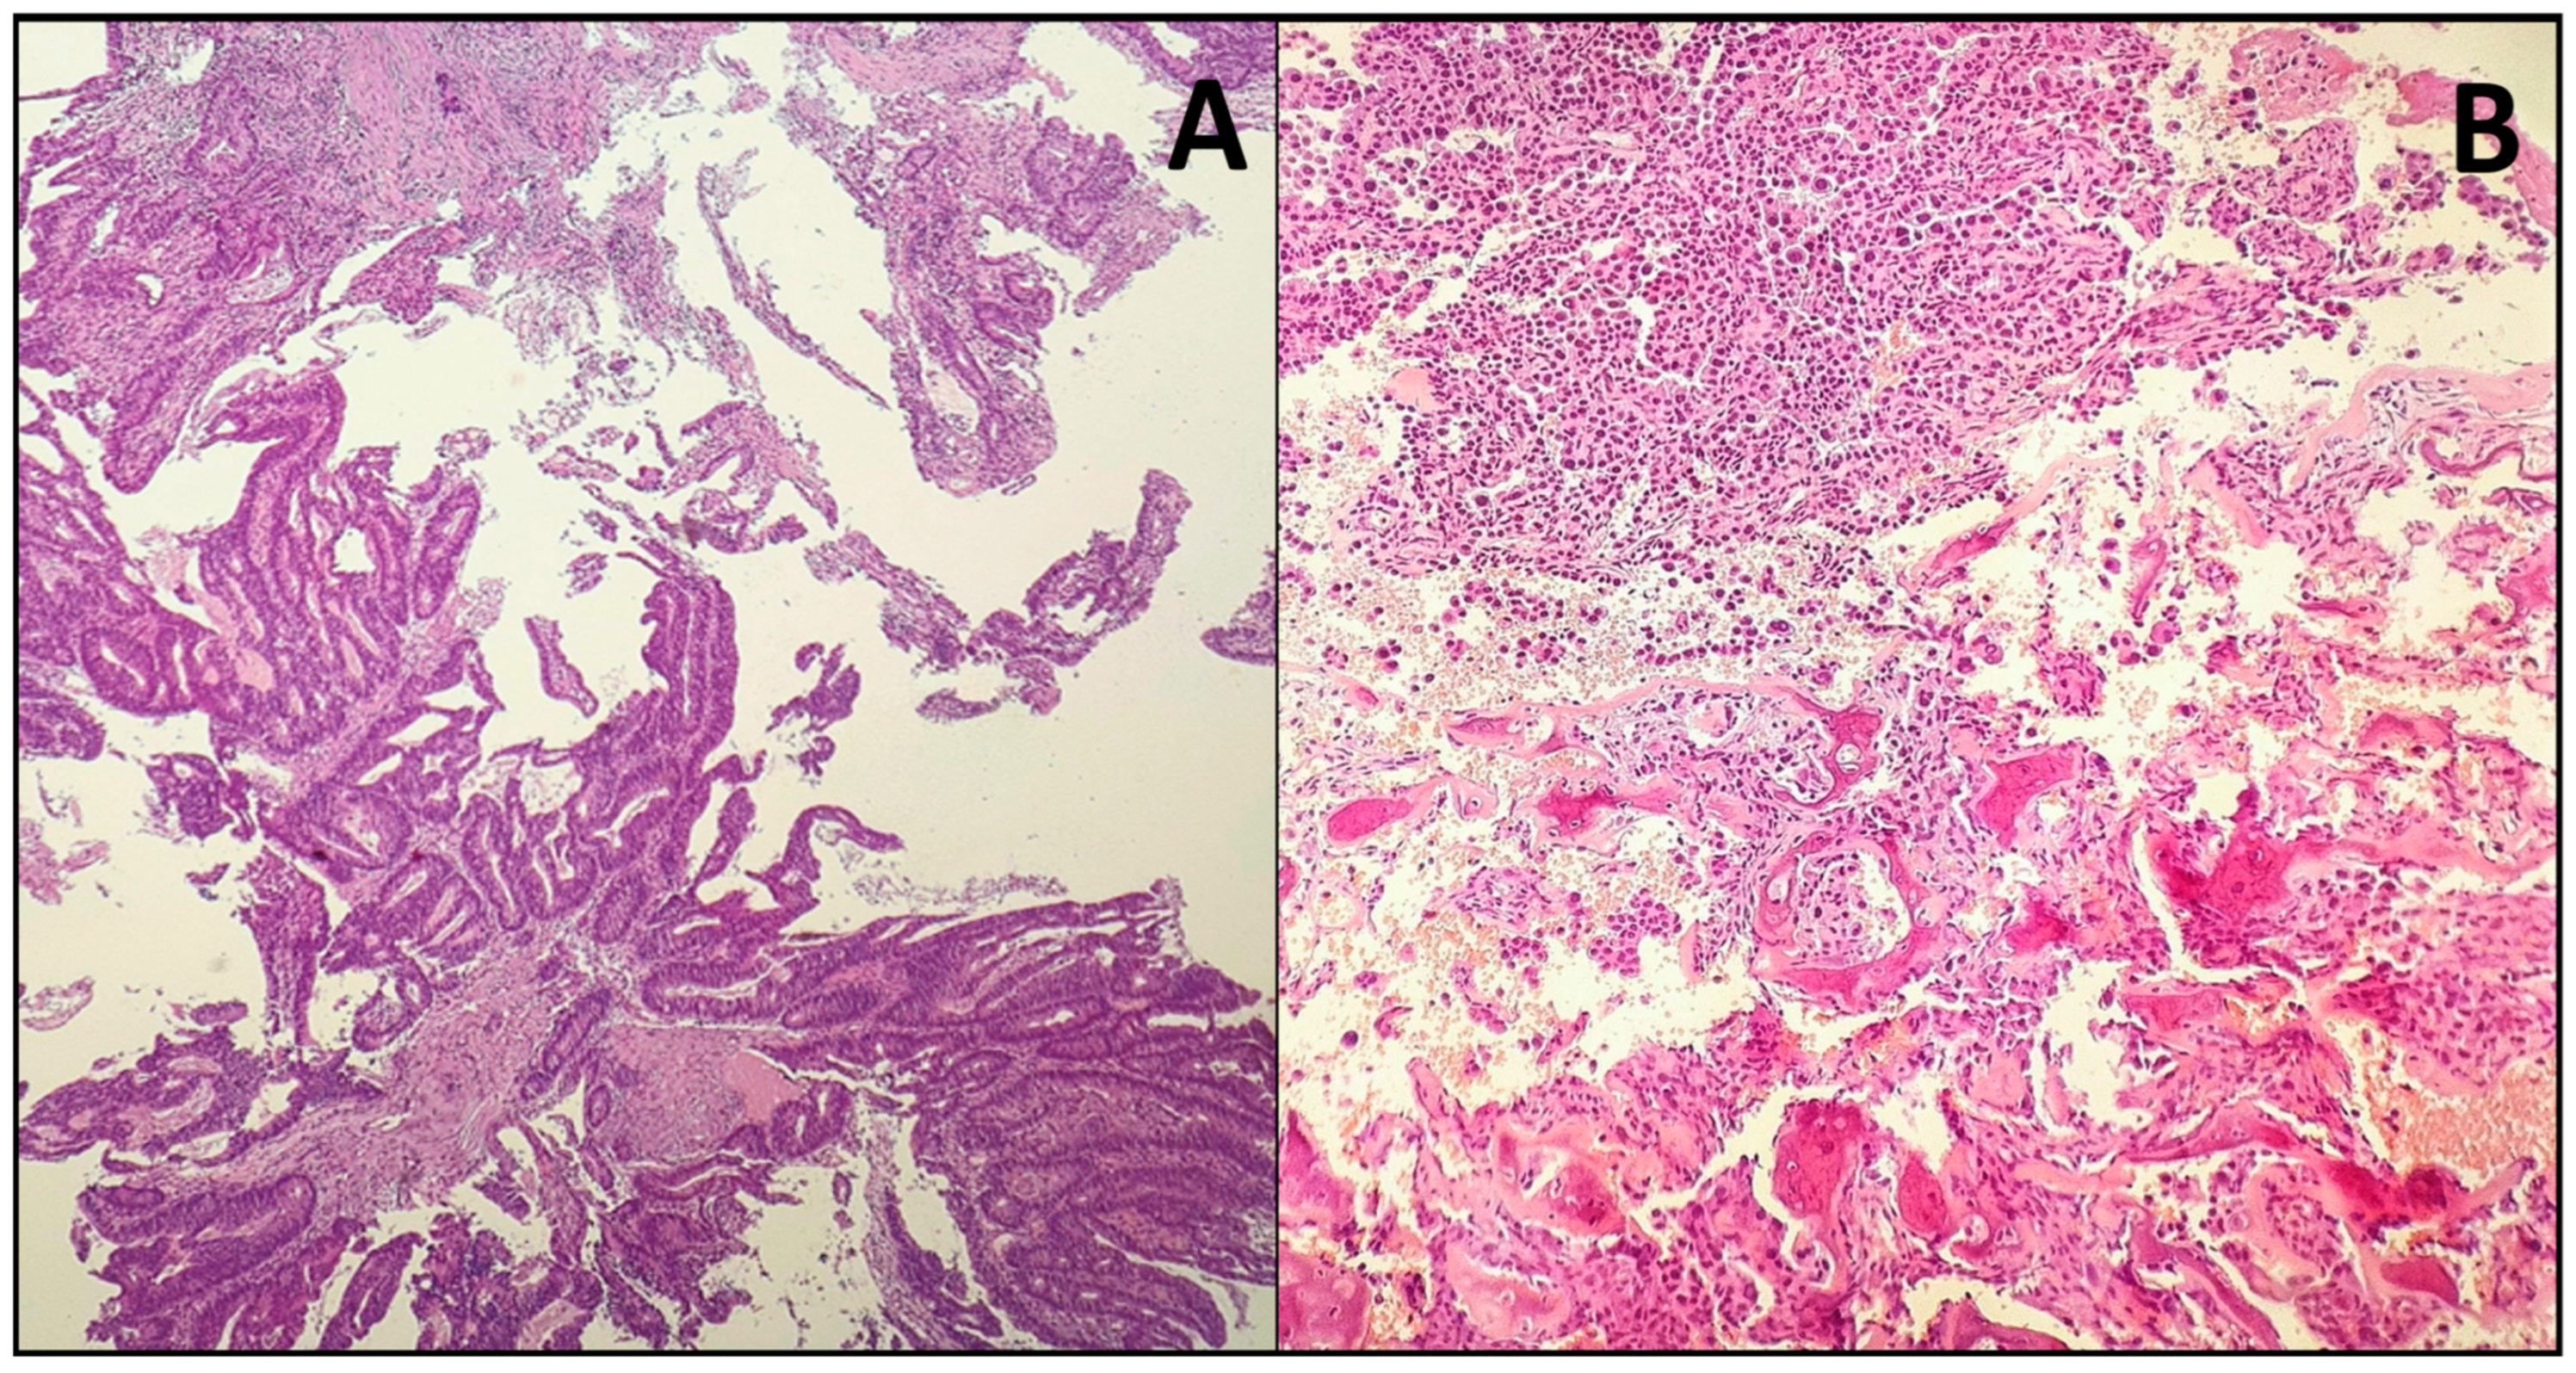

2.4. Histopathology

| Histopathology | Resembles colorectal adenocarcinoma; forms glandular, papillary, colonic, solid, or mucinous patterns. | Low-Grade: Papillary or glandular patterns with minimal atypia. <br> High-Grade: Solid growth patterns with significant nuclear pleomorphism and necrosis. |